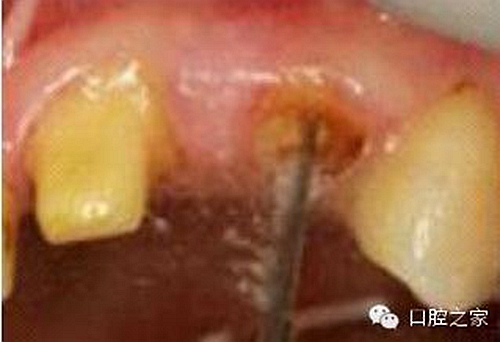

圖3:根管內(nèi)殘留物

圖4:超聲去除根管殘留物?! ?/p>

根管壁殘留物的存在直接影響著纖維樁的粘接和固位,是纖維樁脫落的主要原因之一。由于圓形的根管鉆和根管形態(tài)不完全一致,終鉆預(yù)備完成后大多情況下樁道側(cè)壁會(huì)有不同程度的牙膠和封閉劑等殘留物附著(圖 3)。因此,建議X線檢查根管預(yù)備情況,選用超聲潔牙機(jī)更換較細(xì)工作尖進(jìn)入根管,徹底去除樁道根管壁上附著的殘留物(圖4)。使用根管銼去除殘留物時(shí),很難清除干凈;禁止使用牙膠溶劑如丁克除、氯仿等有機(jī)溶劑去除殘留物,以免破壞根尖區(qū)牙膠的封閉,或有機(jī)溶劑粘附于根管壁形成蠟?zāi)ざ绊懻辰印?#pages##